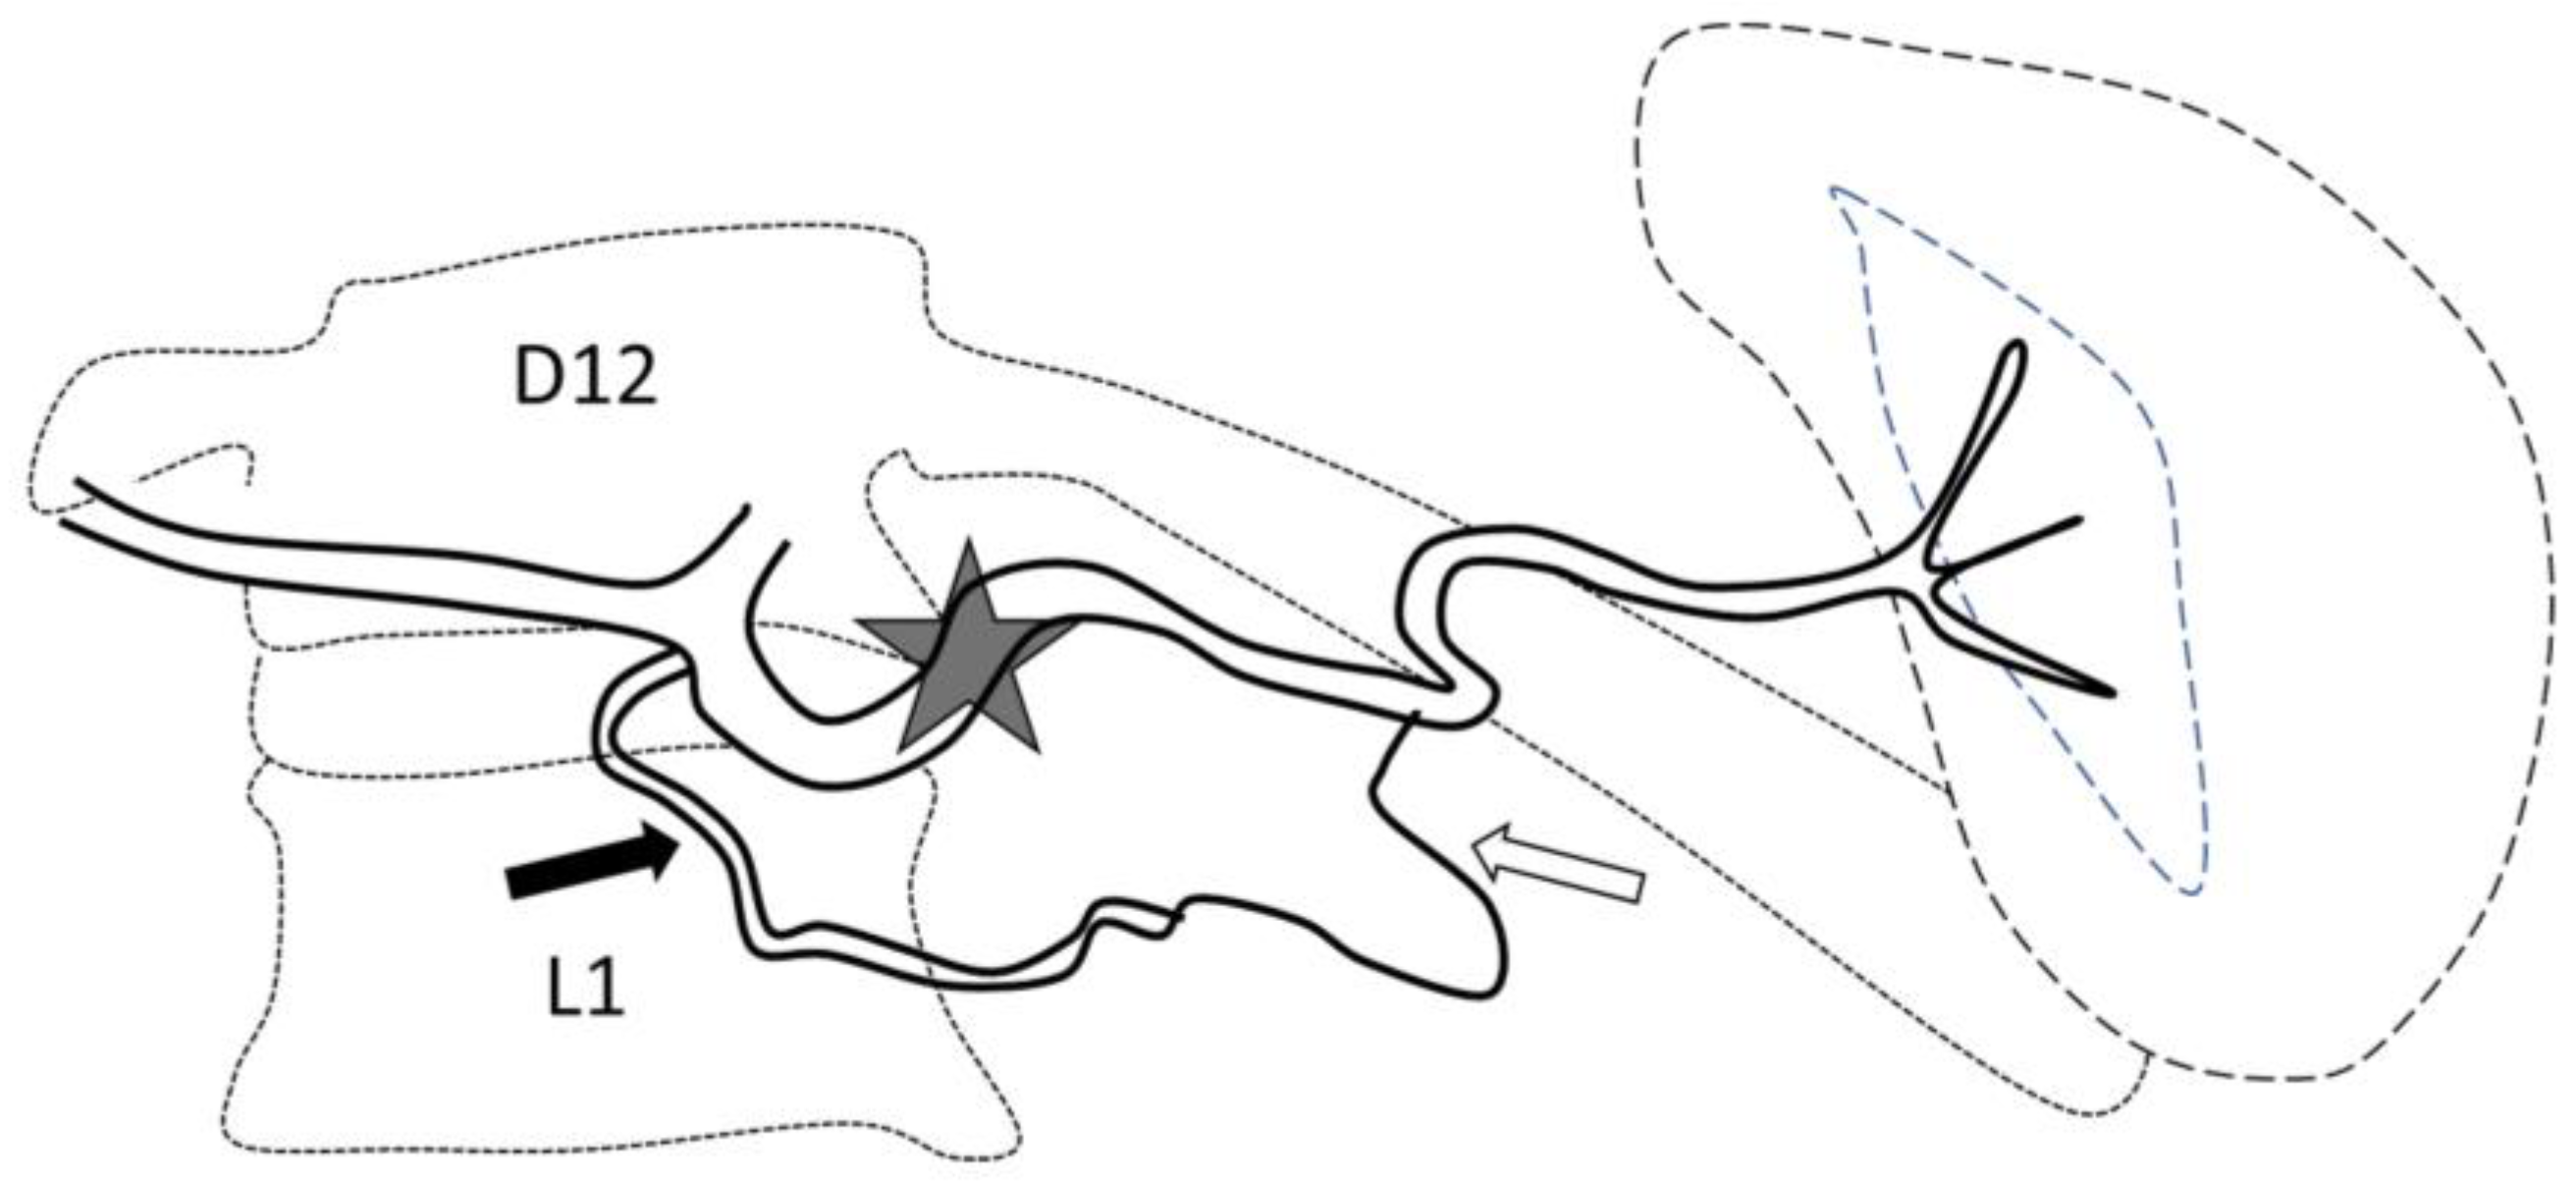

Figure 1.

Optimal site of preventive proximal splenic artery embolization. The optimal site of embolization (star) is downstream from the dorsal pancreatic artery (arrow) and upstream of the great pancreatic artery (blank arrow). Classically, at the left edge of the spine.